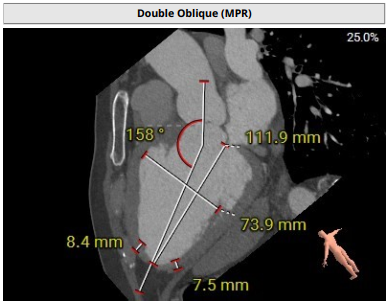

术前影像评估提示,患者主动脉为TYPE0型二叶瓣,瓣叶增厚,边界显示不清,疑似瓣叶脱垂,少量钙化。主动脉瓣环直径31.5mm,左心室流出道直径35.3mm,STJ直径32.3mm,升主动脉直径37.3mm,冠脉开口高度充足(左冠15.6mm,右冠19.1 mm),左室与主动脉夹角158°。

该患者心脏结构对于手术存在一定挑战,主要在于患者为主动脉TYPE0型二叶瓣,左右冠同窦,瓣窦部扩张,窦部最大径线42.7mm,最终手术团队根据患者解剖结构,将两枚夹持件放入同一窦内,第三枚夹持件放置在无窦内。此外,患者同种异体原位肝移植术后2年,长期服用抗排斥药物,行传统体外循环下的心脏手术风险较高。